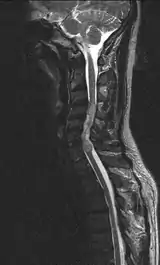

| Ependymoma of the cervical spine, completely obscurating the spinal canal |